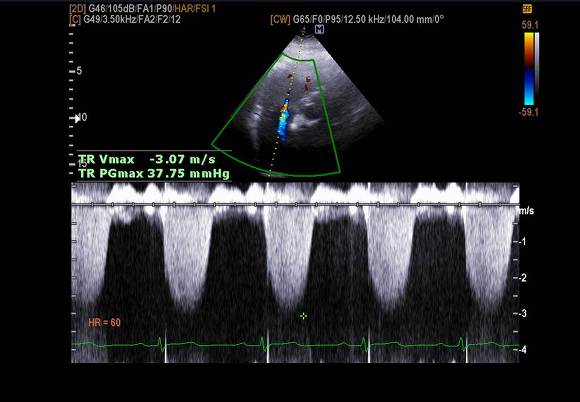

pic 4. TR velocity (37mmHg) -pulmonary hypertension (+)